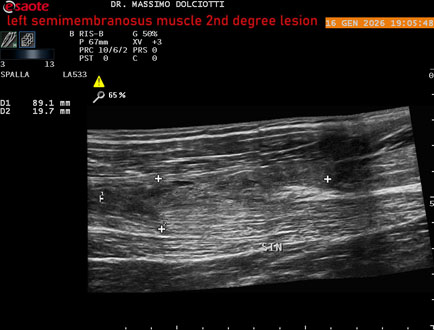

Data inserimento: 23/01/2026

Ecografia del: 16/01/2025

Strumento: Esaote MyLab Eight

Sonda: Lineare Multifrequenza 3-13 MHz

Età Paziente: M 23 anni

Motivazione dell'esame: dolore coscia sinistra da tre giornii.

Commento all'esame: le immagini ed il video documentano il muscolo semimembranoso sinistro disomogeneo per area iso-ipoecogena delle dimensioni di 38 x 14,7 mm per asse corto trasversale, 81 x 22 mm per asse longitudinale, come da lesione di 2° grado, con minimo versamento siero-ematico intramuscolare.

Conclusioni: lesione di 2° grado del muscolo semimembranoso sinistro (2nd degree lesion of the left semimembranosus muscle).